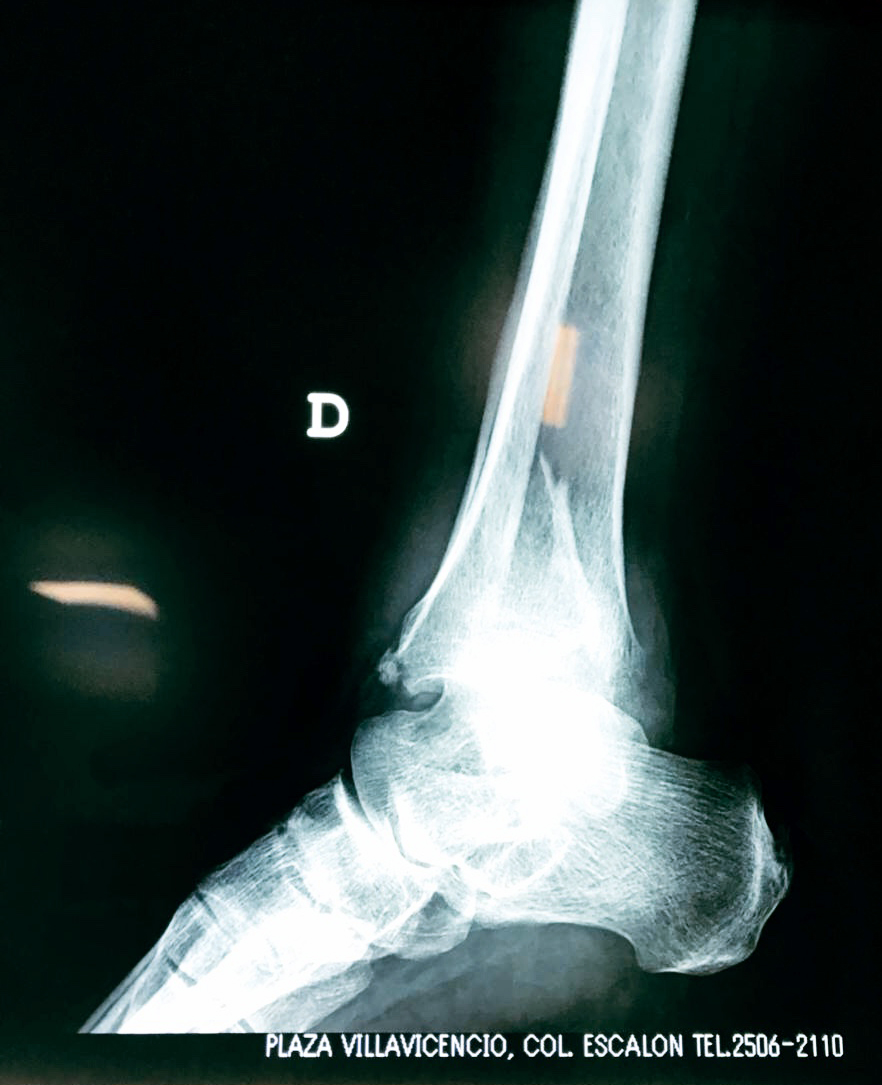

Una fractura de tobillo es la rotura de uno o más de los huesos del tobillo. Estas fracturas pueden ser:

- Los extremos de los huesos están desalineados entre sí (desplazados).

- La fractura se extiende hasta la articulación del tobillo (fractura intra-articular).

Cuando se necesita cirugía, es probable que esta implique el uso de clavijas de metal, tornillos o placas para sostener los huesos en su lugar mientras la fractura se consolida. Los elementos de soporte pueden ser temporales o permanentes.